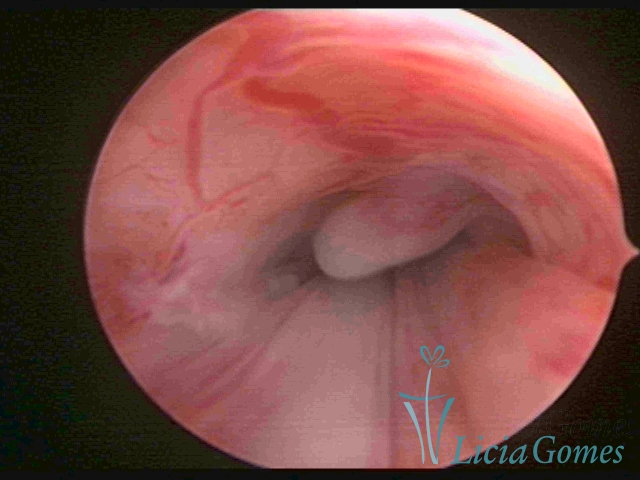

PÓLIPOS ENDOCERVICAIS

São tumores benignos, resultantes da proliferação focal reativa aos processos inflamatórios ou à situações de hiperestrogenismo, e podem ter sésseis (com a base de implantação larga) ou pediculados do epitélio.